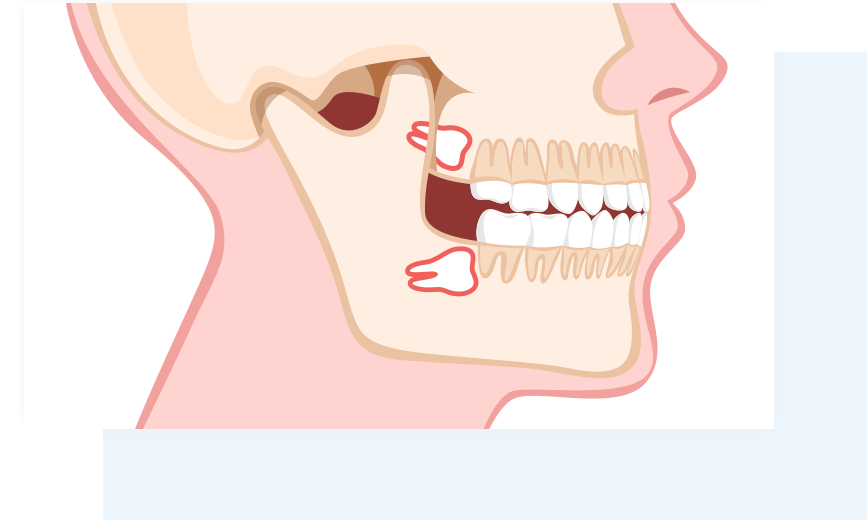

永久歯のなかで一番最後に生えてくる最も後ろの奥歯のことで、正式名称は第三大臼歯といいます。永久歯は通常15歳前後で生え終わり、その後20代前後から上顎の左右に2本、下顎の左右に2本の合計4本生えてきますが、生え方が真っ直ぐでないケースも多いです。

隣の歯にあたる

真横に生える

歯茎に埋もれる

親知らずが埋もれている、横向きに生えているなど正常な生え方でない場合、磨きにくさから虫歯や歯周病になりやすく、炎症や腫れが起こったり、歯槽骨へ吸収されてしまうことがあります。親知らずの抜歯は、虫歯や歯周病のリスクの低減、第二大臼歯の保全、歯列不正の予防など様々なメリットがあります。